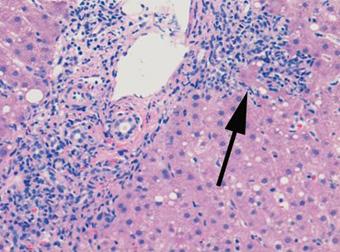

La miocarditis es una enfermedad inflamatoria del músculo cardíaco, diagnosticada mediante biopsia endomiocárdica.

Biopsia de miocardio:

Mediante cateterismo cardíaco y biopsia asistida por resonancia magnética

Se indica en casos de Insuficiencia cardíaca de nueva aparición, arritmias graves y resistencia al tratamiento